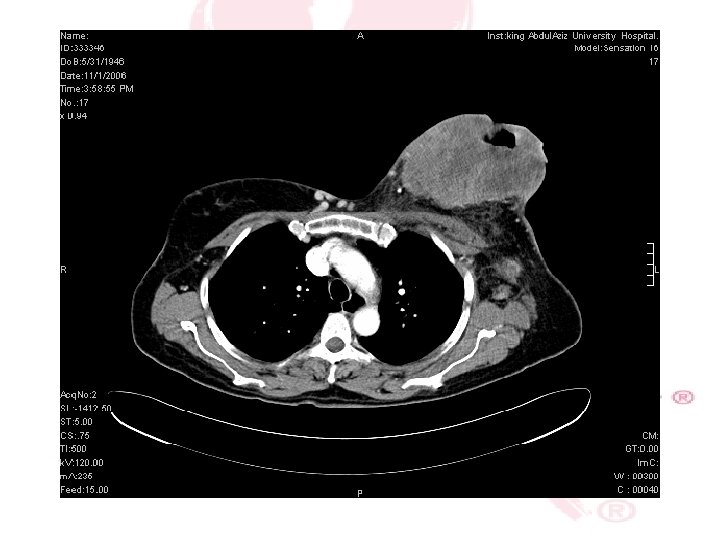

CT SCAN CHEST , ABDOMEN &PELVIS